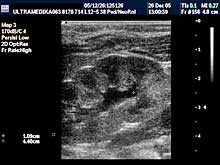

C) UZ dijagnostika kukova

Ultrazvnučni pregled kukova je neophodan u

prvom mesecu života.

Ovaj neinvazivni pregled omogućava tačnu procenu nezrelosti

ili iščašenja kuka i obično je dovoljno informativan za određivanje

načina lečenja. Dalja procena rasta kuka je takođe u domenu UZ

dijagnostike. Nema potrebe naglašavati da se deca rađaju sa

oboljenjima kukova koji se ne moraju obavezno kliničkim pregledom

prepoznati. Najvažniji preduslov za adekvatno lečenje nezrelosti

kukova je što ranije postavljena dijagnoza (inače dijagnoza nezrelosti

kukova je moguća u toku UZ pregleda trudnoće). Jedini razlog za

odlaganje pregleda je posedovanje neadekvatne ultrazvučne opreme.Primenjena tehnika: 2D broad band, program za automatsko izračunavanje

stepena nezrelosti po Grafu. Ultrazvučna sonda od 5-12 MHz(megaherca)